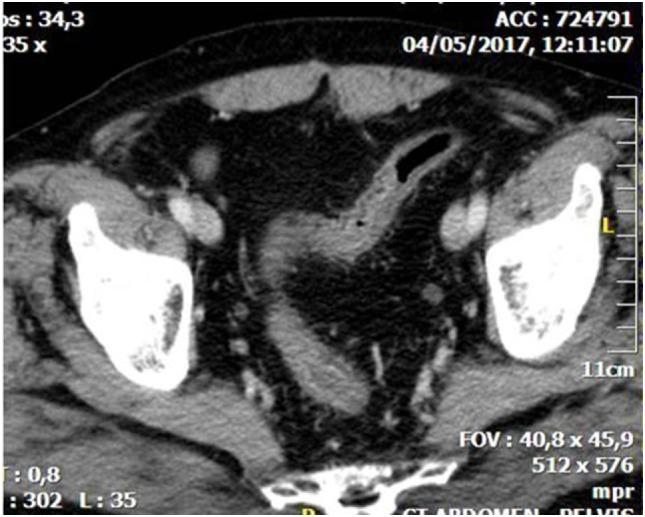

IC is usually a transient disease, but it can also cause gangrene of the colon, requiring emergency surgical exploration. Diagnosis is troublesome and is based on imaging examinations, mainly computerized tomography, which in association with colonoscopy can delineate the distribution pattern and severity of disease.

IC通常是一种短暂性疾病,但也可导致结肠坏疽,需要紧急手术探查。诊断较为棘手,基于影像学检查,主要是计算机断层扫描,其与结肠镜检查相结合可描绘疾病的分布模式和严重程度。